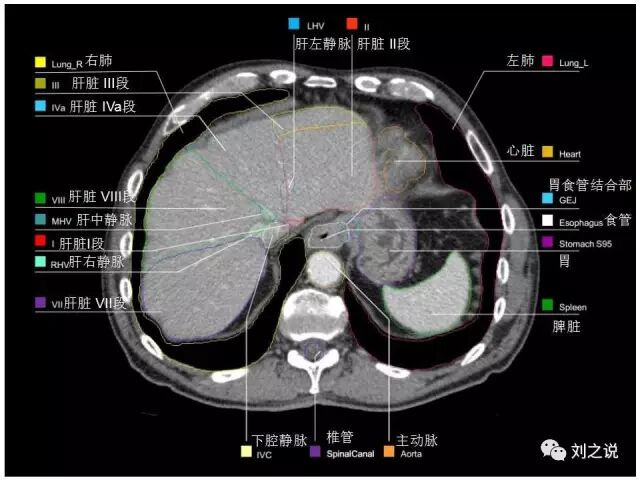

参考RTOG共识和3D-body解剖。

来源:刘之说